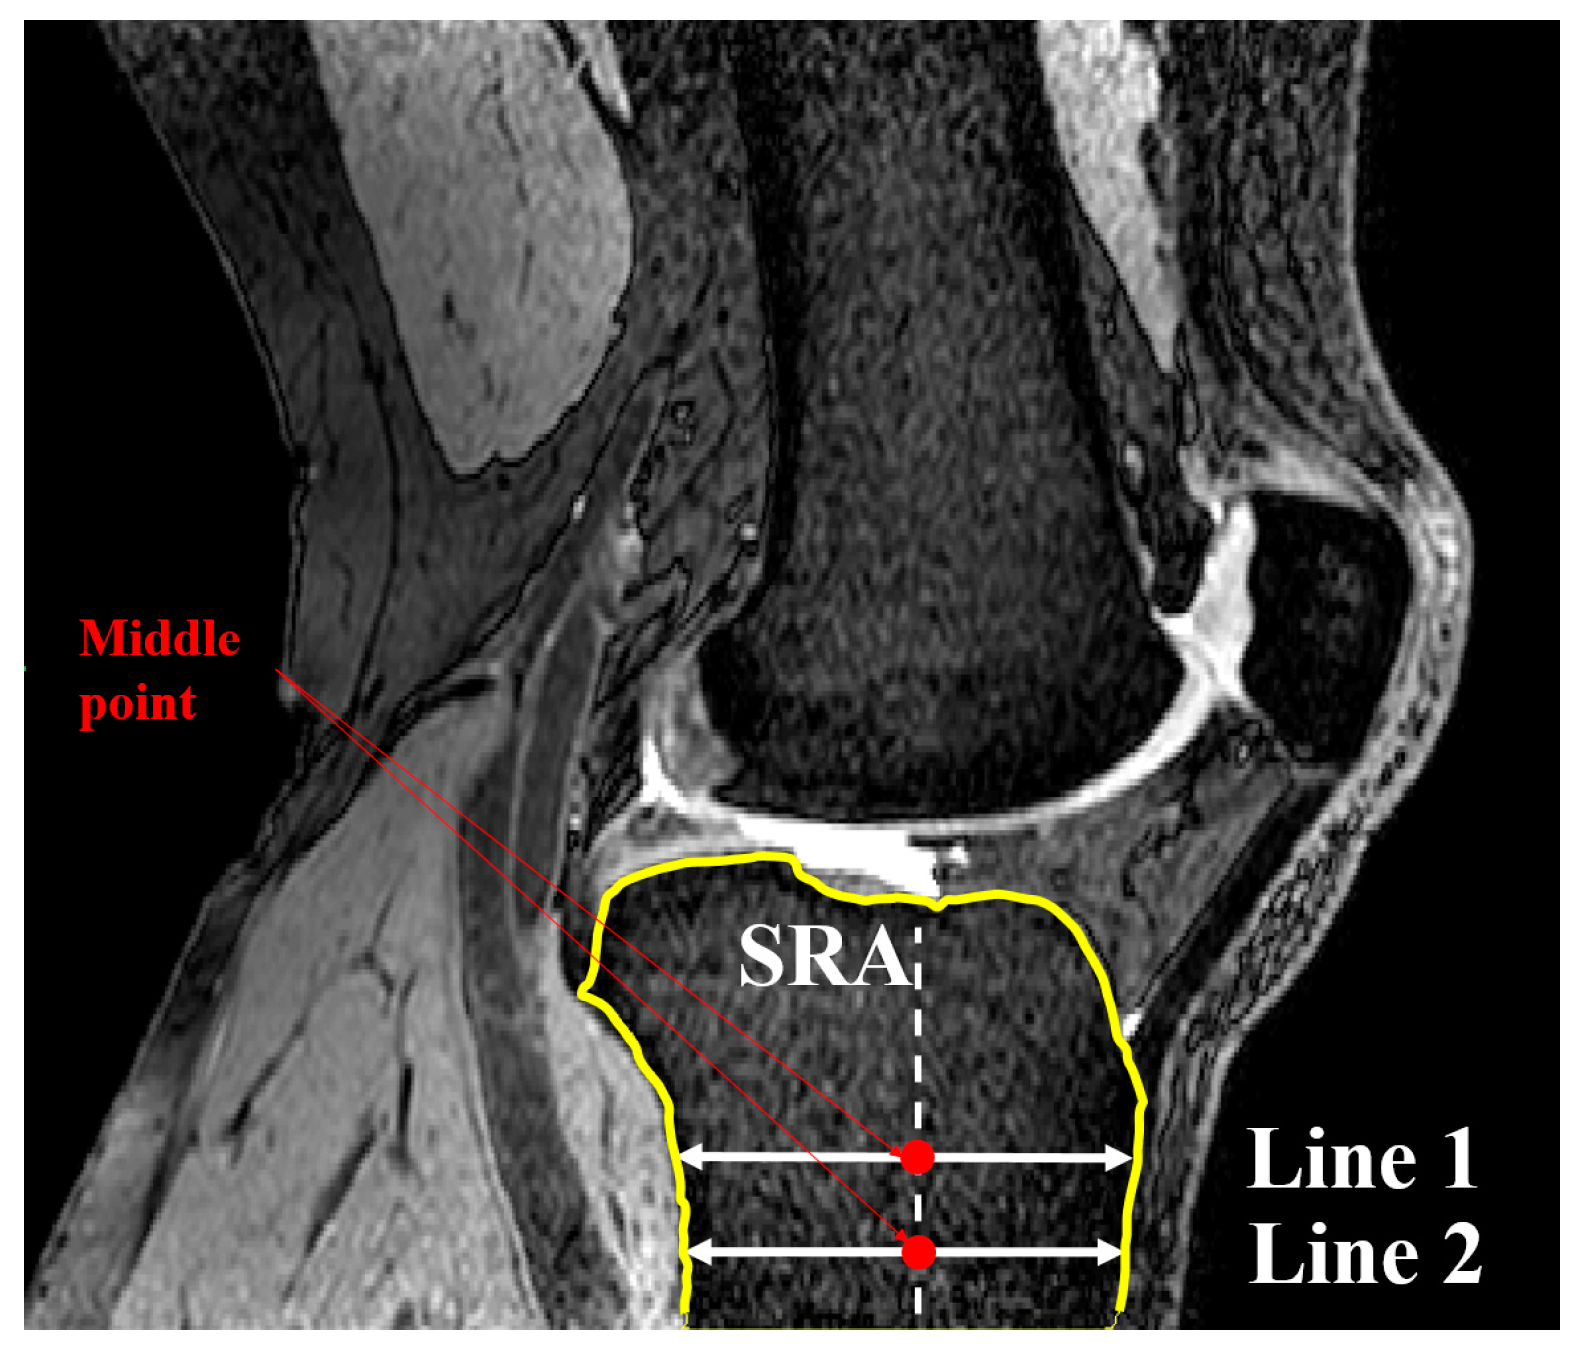

2.1. Medial and Lateral Tibial Slope Measurement Methodology

2.2. Coronal Tibial Slope Measurement Method